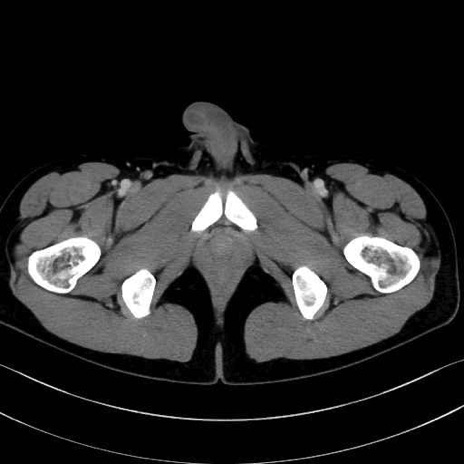

4. 深層外旋六筋(股関節の深部)

梨状筋 (Piriformis)

内閉鎖筋 (Obturator internus)

外閉鎖筋 (Obturator externus)

大腿方形筋 (Quadratus femoris)